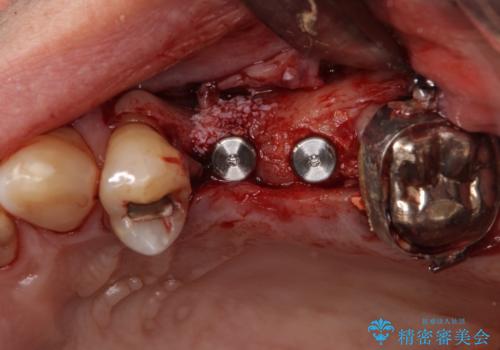

ブリッジの支台を抜歯したことで2本のインプラントが必要であり、その後方はインプラント埋入に必要な骨量が不足していたため、上顎洞粘膜の挙上を行うこととしました。

また、残っている最後方歯は手前に倒れてきていたため、部分矯正により奥に移動させてから、インプラント埋入を行うこととしました。

部分矯正期間中はアンカースクリューやフック、ゴムなどが粘膜にあたり、大変な思いをすることになりましたが、そのおかげでインプラント補綴した歯と最後方歯の位置が非常に良好となり、まるでご自身の歯のように咬むことができるようになりました。